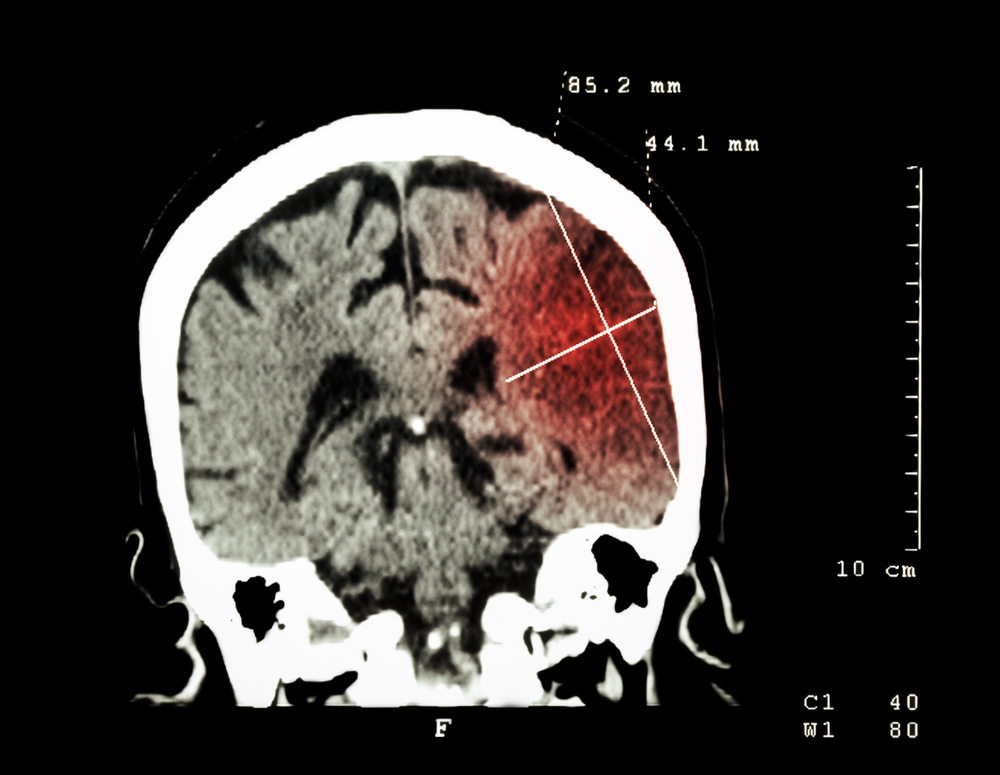

Гематома головного мозга

Гематома головного мозга – это ограниченный участок скопления крови в полости черепа. По отношению к головному мозгу и его оболочкам различают несколько видов гематом....